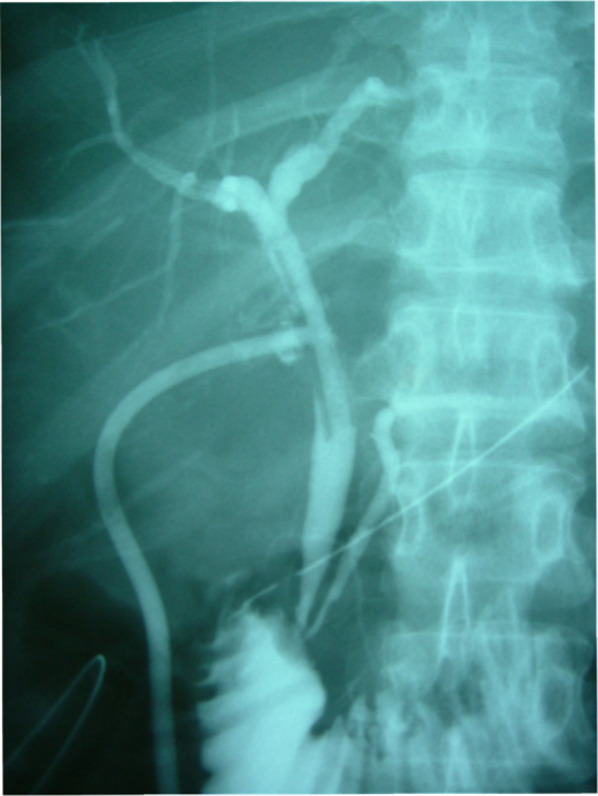

A 30-year-old woman was transported to our hospital by ambulance due to epigastric pain. A laboratory analysis revealed the following: white blood cells, 4000/mm3; total bilirubin, 3.0 mg/dL; alkaline phosphatase, 640 IU/L; GOT, 395 IU/L; GPT, 746 IU/L; and amylase, 37 IU/L. Abdominal CT demonstrated multiple gallbladder (GB) stones without inflammation of the GB; the diameter of the common bile duct (CBD) was 10 mm. ERCP was performed under the suspicion of CBD stones. Bile duct cannulation was easily performed. Cholangiography revealed no apparent CBD stones. Although EBD is not routinely carried out in this situation, we carefully performed EBD due to the suspicion of CBD stones, and carefully taking the clinical course into consideration. Before the procedure, a dilatation balloon (Hurricane RX Rapid Exchange, Boston Scientific, MA, USA) was inflated as a precaution in order to check the condition of the balloon. The dilatation balloon was then passed over the guidewire and located at the site of the biliary sphincter. The balloon was inflated to 2 atmospheres of pressure. After the procedure, the balloon suddenly burst. We were unable to remove the EBD catheter because the balloon was caught at the biliary sphincter (Figs. 1, 2). A computed tomography (CT) scan showing the burst balloon located at the site of the biliary sphincter (Fig. 3). Finally, we had to perform surgical intervention to remove the EBD. We made an incision at the pylorus, and then we manually pulled the EBD catheter through this incision, as shown in Fig. 4a, b. The broken catheter was successfully removed without injuring the biliary sphincter. Cholecystectomy, CBD exploration, and then removal of the CBD stone were performed. A T-tube was inserted for drainage. Intra-operative cholangiography revealed no residual stones and no biliary sphincter abnormality (Fig. 5). The burst balloon of the EBD catheter is shown in Fig. 6. The patient was discharged without any complications after removal of the T-tube on post-operative day 14.

Regarding the surgical technique, we think that there were three important considerations in the surgical removal of the burst balloon of the EBD catheter that was trapped at the biliary sphincter. First, we made the incision at the pylorus to remove the catheter, based on the consideration that an incision at the 2nd portion of the duodenum would increase the risk of post-operative complications (e.g., duodenal stenosis or leakage). Second, we preformed cholecystectomy and intra-operative cholangiography because residual stones were present in the CBD. Third, we had to pay attention to biliary sphincter edema and dysfunction induced by the burst balloon. Thus, a T-tube was inserted into the CBD after CBD stone removal.